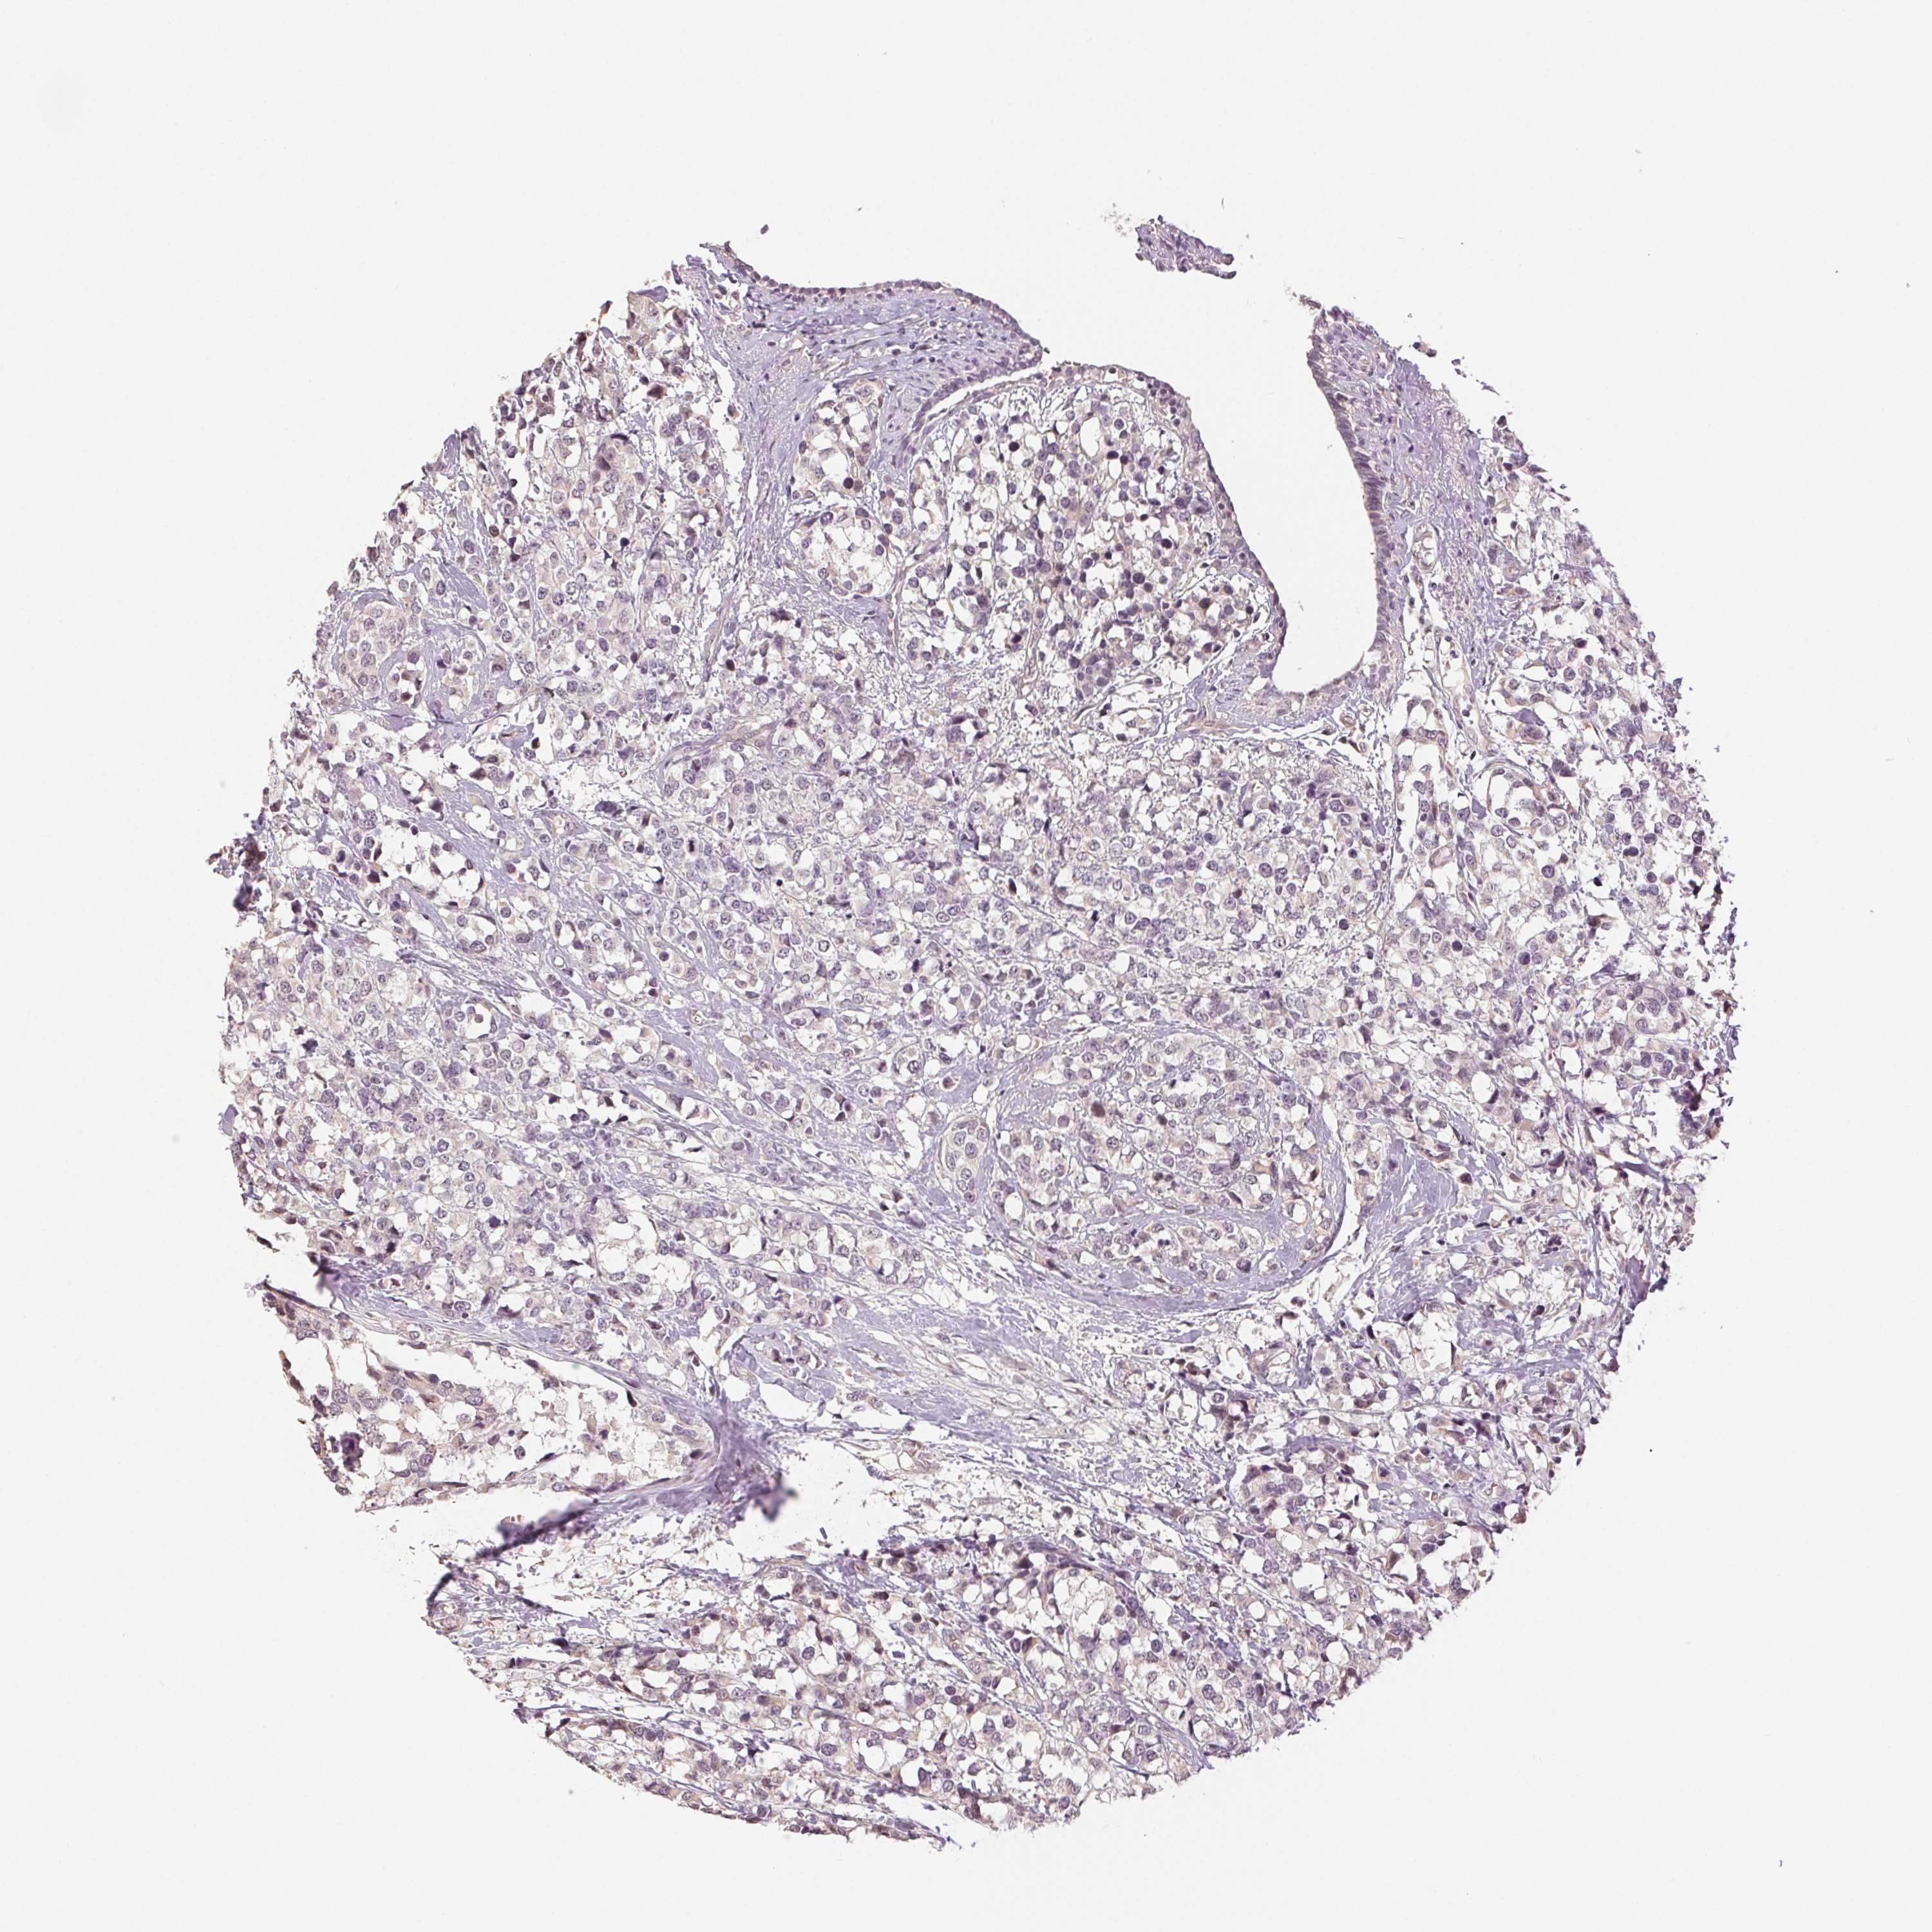

CANCER BREAST CANCER Show tissue menu

BRCA TCGA BRCA VALIDATION PROTEIN EXPRESSION

Breast cancer

Human cancer